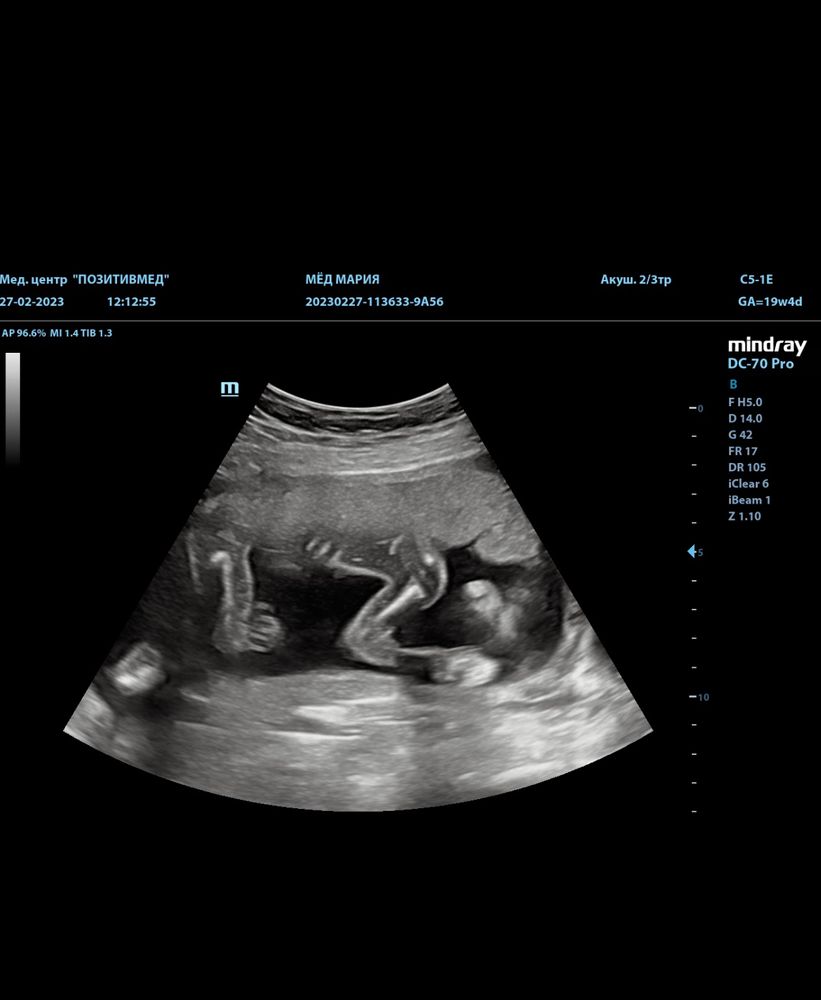

Второй скрининг, наша длинноногая принцесса😌🥰